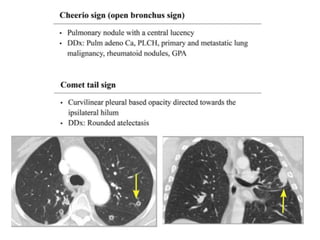

PARENCHYMAL SIGN

• Air Crescent Sign

• Monod Sign

• Halo Sign

• Atoll Sign

• Cheerio Sign

• Comet Tail Sign

• Mosaic Sign

• Head Cheese Sign